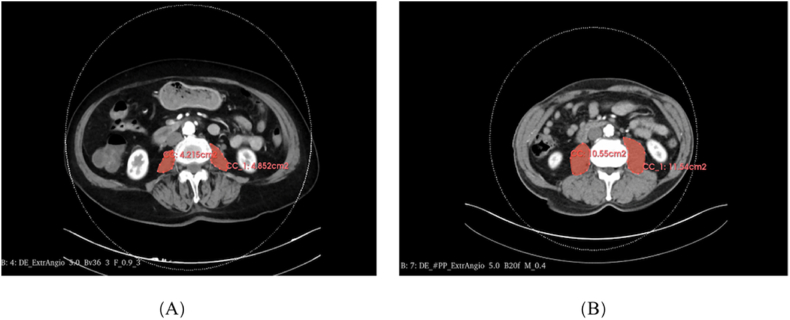

The correlation between CT images of the third lumbar vertebra (L3) and overall muscle mass has been well-established and extensively documented [11]. In this study, the CT scans of PAD patients were delineated using 3D Slicer software (version 5.1.0, American). The methodology enabled the semi-quantitative and semi-automatic assessment of the bilateral psoas muscle's cross-sectional area at the lower margin of the L3 vertebra (Fig. 1 A, B). The psoas muscle index (PMI, cm2/m2) was then determined using the formula:

Measurement of psoas muscle areas from computed tomography slices at the level of the third lumbar vertebra. The lumbar-muscle areas of peripheral arterial disease (PAD) patients with sarcopenia (A) and without sarcopenia (B).

Gender-specific PMI thresholds, as prescribed in established guidelines, were used to diagnose sarcopenia. Specifically, men with a PMI <5.5 cm2/m2 and women with a PMI <4.0 cm2/m2 were identified as having sarcopenia [8,18,19])